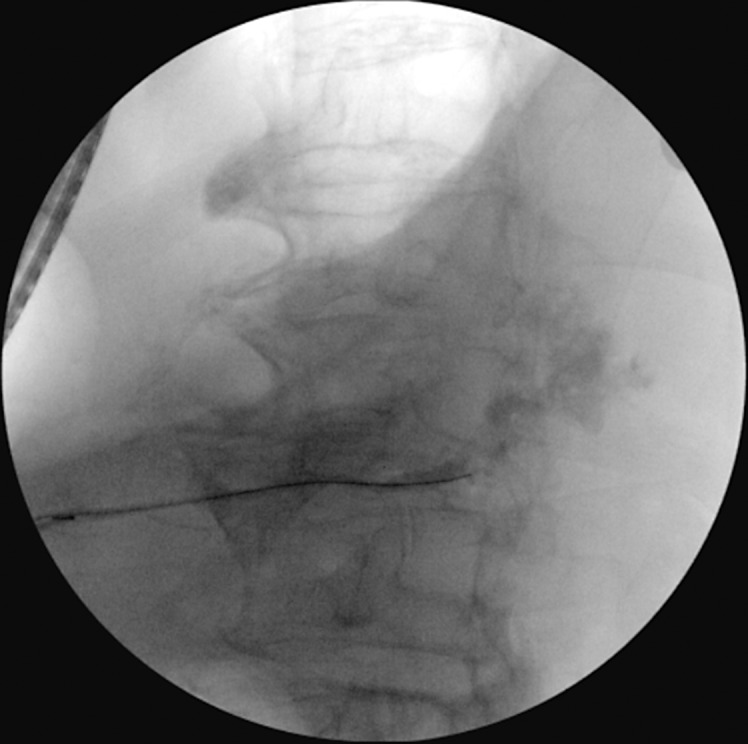

Case presentation: We present the case of a 79-year-old male with severe colitis resulting in perforation and pericolonic abscess formation adjacent to the pancreas, which resulted in an internal pancreatic fistula and pancreatic ascites. After 2 paracenteses, our patient ultimately underwent endoscopic retrograde cholangiopancreatography (ERCP) with sphincterotomy and pancreatic duct stent placement. The patient clinically improved and was ultimately discharged.

Conclusion: Follow-up ERCP was performed 2 months after discharge and showed no contrast extravasation, illustrating closure of the previous pancreatic fistula. Ultimately, our case demonstrates that cases of severe colitis may contribute to adjacent pancreatic fistula and ascites formation.